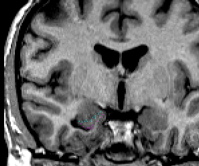

| Segmentation  Part I - Anterior portion of the amygdala  The second slice of the amygdala should be segmented using the same methodology. The only difference is that the amygdala may touch the cortex on this slice. Also, it may be possible to see the lateral extent of the amygdala on this slice. If that is the case, use a contour line to accurately capture this border of the amygdala. | |

|  | Part II - Medial portion of the amygdala As you move posteriorly, the amygdala becomes easier to visualize. Use a contour line to give the general outline of the amygdala, then check the other views available to you to confirm this outline. When the amygdala is in its full extent, it is fairly easy to see in the coronal view. Remember that the amygdala has a very small wave that crests over the choroidal fissure. Refer to an atlas to see this wave more clearly. Alter the brightness of the screen so that you can adequately see the strip of white matter that separates the amygdala from the cortical areas. |